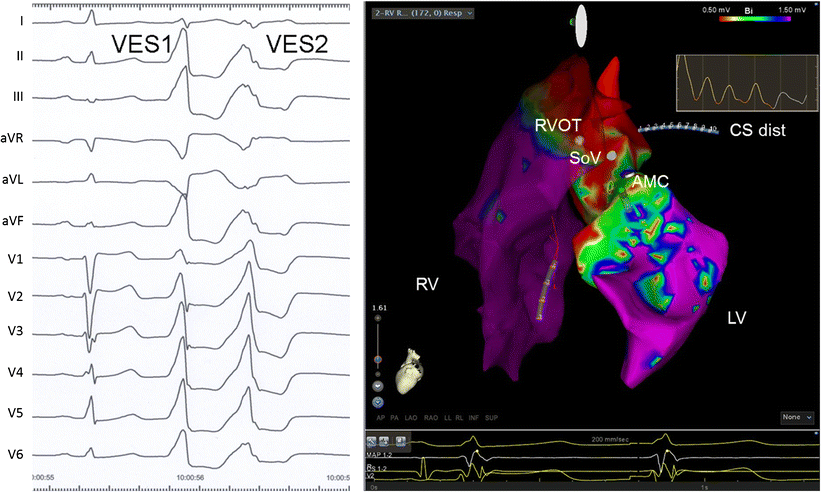

Ventriküler Taşikardi Kateter Ablasyonu

• Ventriküler taşikardi (VT), kalbin alt odacıklarından (ventriküllerden) kaynaklanan, normalden hızlı (genellikle dakikada 100 atımın üzerinde) ve düzensiz kalp ritmidir. Bu durum, kalbin kan pompalama işlevini önemli ölçüde etkileyebilir ve ciddi sonuçlara yol açabilir.

• Kateter ablasyonu, lokal anestezi altında kasık bölgesinden damar yoluyla kalbe ince tüpler (kateterler) yerleştirilerek yapılır. Özel haritalama sistemleri kullanılarak aritminin kaynağı belirlenir ve radyofrekans enerjisi veya kriyoablasyon yöntemiyle bu bölge etkisiz hale getirilir. İşlem genellikle 2-4 saat sürer.

• VT ablasyonunun başarı oranı, altta yatan kalp hastalığının tipine ve VT'nin özelliklerine göre değişmektedir:

• İdiyopatik VT'lerde (yapısal kalp hastalığı olmayan) başarı oranı %80-95

• İskemik kardiyomiyopatide %60-75

• Non-iskemik kardiyomiyopatide %50-70

Bazı hastalarda tekrarlayan işlemler gerekebilir ve uzun dönem başarı için hasta takibi önemlidir.